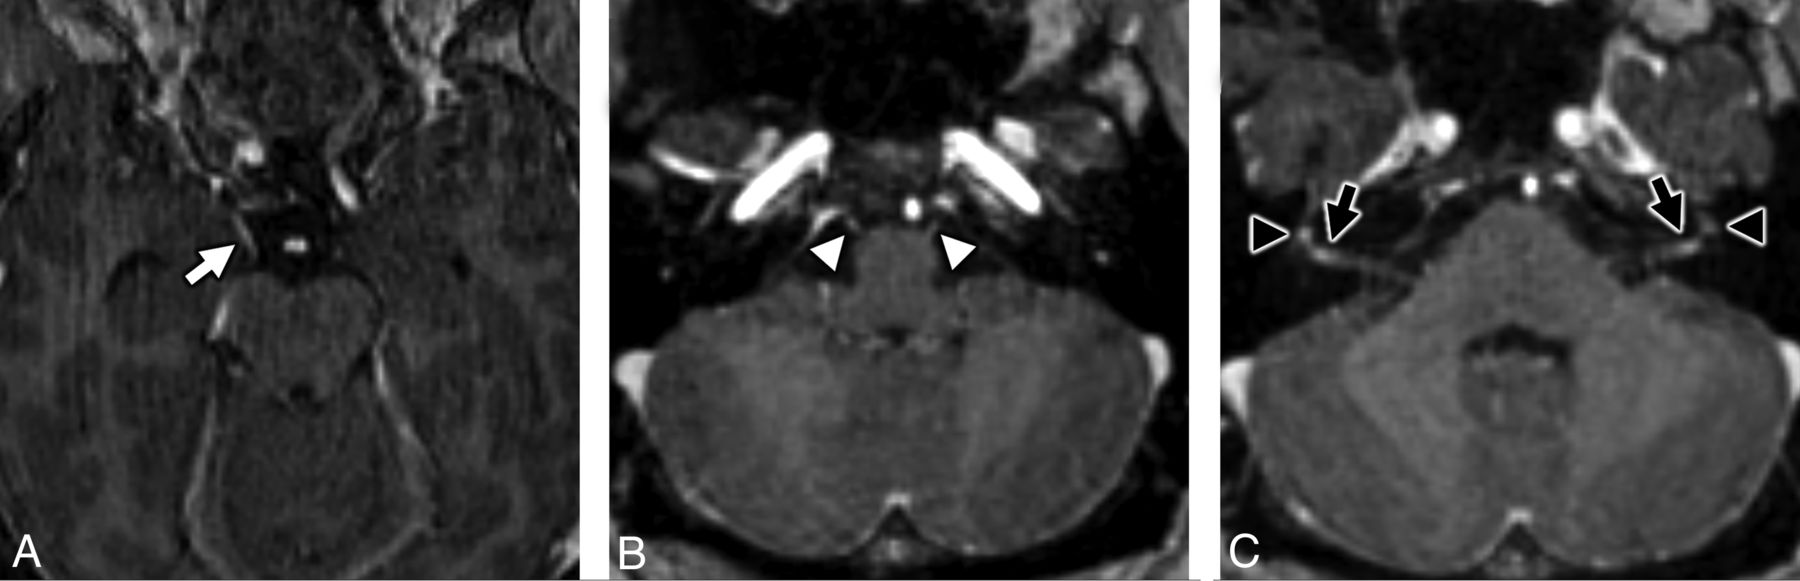

He initially did well with convalescence at home, but on day 16 of illness, he began to experience right-sided facial numbness and weakness. During 24 hours, his symptoms became bilateral and resulted in severe dysarthria, necessitating a return to the emergency department. He also reported associated hypogeusia. Neurologic examination demonstrated a bilateral lower motor neuron pattern of facial weakness with otherwise normal cranial nerve (CN) examination findings, preserved strength and sensation in all extremities, and intact muscle stretch reflexes. He was admitted for observation and underwent MR imaging of the brain and temporal bones, as well as fluoroscopically guided lumbar puncture for CSF sampling. The CSF was negative for bacterial culture and stain and demonstrated normal glucose levels (65 mg/dL), no leukocytes, and mildly elevated protein levels (49 mg/dL). MR imaging demonstrated abnormal enhancement of thefacial (CNVII) and abducens (CNVI) nerves bilaterally, as well as the right oculomotor nerve (CNIII) (Figs 2–4).

MR imaging of the temporal bones in a patient with antecedent COVID-19 and new-onset bifacial weakness and paresthesia subtype Guillain-Barré syndrome. Coronal postcontrast T1-weighted fat-saturated MR imaging of the right (A) and left (B) temporal bones demonstrates abnormal “tuft-like” enhancement at the anterior-superior fundus of the internal auditory canal bilaterally (white arrows), corresponding to the distal canalicular segments of the facial nerves (CNVII). Note additional contrast enhancement along the tympanic segments of the facial nerve bilaterally (white arrowheads), which is greater in degree than typically encountered. Enhancement along the canalicular segments of the facial nerves (white arrows) is always considered abnormal on MR imaging, though mild tympanic segment enhancement is considered within normal limits.

MR imaging of the temporal bones in a patient with antecedent COVID-19 and new-onset bifacial weakness and paresthesia subtype Guillain-Barré syndrome. Axial postcontrast T1-weighted fat-saturated MR imaging of the temporal bones (A) shows subtle-but-abnormal enhancement along the cisternal segments of the abducens nerves (CNVI) bilaterally (white arrows), as well as subtle enhancement along the tympanic segments of the intratemporal facial nerves (CNVII) bilaterally (white arrowheads). Coronal postcontrast T1-weighted fat-saturated MR imaging (B) shows subtle asymmetric enhancement along the cisternal segment of the right oculomotor nerve (CNIII, black arrow).

MRI of the brain in a patient with antecedent COVID-19 and new onset bifacial weakness and paresthesias subtype Guillain-Barré syndrome. Axial post-contrast T1-weighted SPoiled Gradient-Recalled (SPGR) MRI shows abnormal enhancement of the right oculomotor nerve (CNIII, white arrow, A), the cisternal segments of the abducens nerves (CNVI) bilaterally (white arrowheads, B), the distal canalicular segments of the facial nerves (CNVII) bilaterally (black arrows, C), and the proximal tympanic segments of the intratemporal facial nerves (CNVII) bilaterally (black arrowheads, C).

Our report details a case of bifacial weakness and paresthesia subtype Guillain-Barré syndrome that was temporally associated with COVID-19. In our case, a patient with antecedent community-acquired COVID-19 pneumonia developed rapidly progressive bilateral facial weakness, extremity paresthesia, and mild proximal extremity weakness without ataxia or other cranial neuropathies 16 days after the onset of COVID-19 symptomatology. He exhibited clinicoradiologic features most consistent with GBS, affecting CNVII bilaterally and lacking antiganglioside antibodies, concordant with prior reports of BFP subtype GBS.8⇓-10 Our patient demonstrated imaging findings that align with prior reports of GBS following antecedent viral infections.11,12 Enhancement of the cranial nerves is a known MR imaging finding in GBS,8,13,14 and most interesting, our patient demonstrated abnormal enhancement of CNVI bilaterally and the right CNIII, which were clinically asymptomatic. On the basis of clinical grounds, we suspect that this indicates subclinical disease in the BFP variant of GBS, rather than the Miller Fisher variant of GBS,15 given lack of ophthalmoparesis and ataxia. Our patient did not demonstrate any typical spinal imaging manifestations of GBS, which may include thickening of the cauda equina nerve roots with enhancement, often with a ventral nerve root predilection.16,17